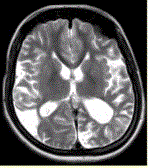

问题 女性,22岁。癫痫发作及智力异常。MRI显示见下图。 有关该病的描述,正确的是

选项 A.多种原因引起颅底大动脉严重狭窄或闭锁,并可见脑底部代偿性异常血管网 B.MRT2WI显示基底节区多发点状血管流空信号 C.DSA显示willis环闭塞,颅底区烟雾状侧支循环 D.CT显示低密度病灶,为缺血、梗死所致,特征是双侧性和多发性 E.影像学首选MRA及MRI F.主要发生在老年人 G.多见于颈内动脉床突上段和大脑前、中动脉近段和基底动脉远端

答案 ABCDEG